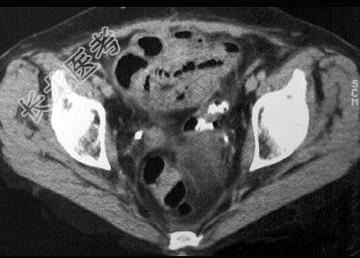

- 单项选择题女,54岁, 直肠癌放疗后一月,阵发性腹痛腹胀, 呕吐应,CT表现如图, 应诊断为 ( )

D、放射性小肠炎